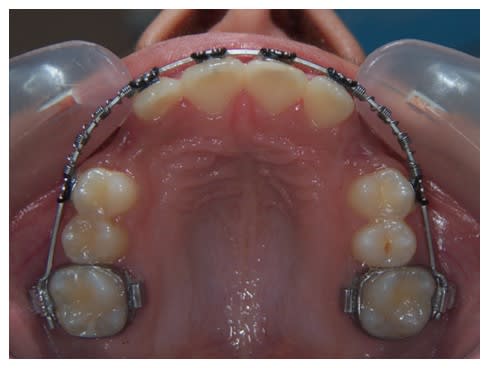

Je pense qu'il est tout à fait possible de trouver la place pour les prémolaires et cela vaut le coup de tenter avant d'extraire quoique ce soit.

Multi attaches uyazzt - Eugenol

Maintenant, on aimerait voir les faces occlusales des dents, et aussi un peu la forme du visage.. S'il y avait une télé, ce serait bien aussi.

Dans cette phase d'interception, le Qhelix et la FEO me semblent pas mal.